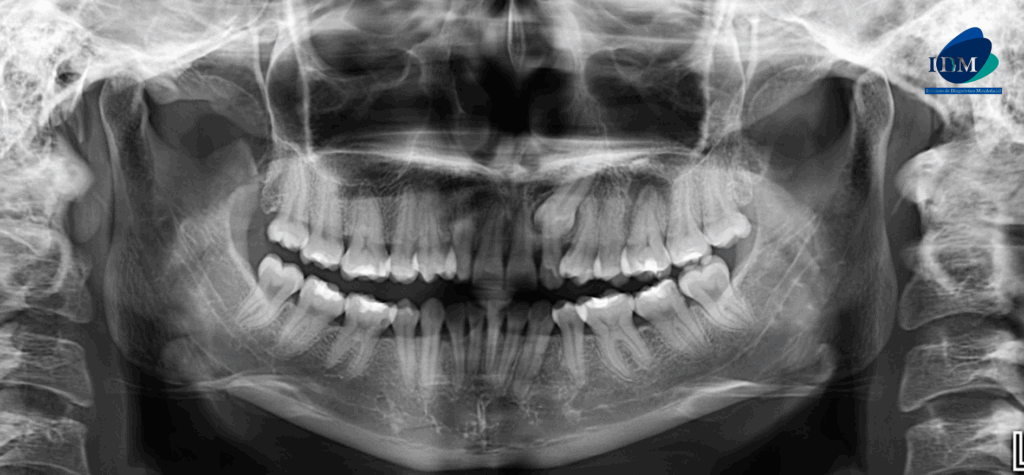

Radiografia Panorámica

A la evaluación de la radiografía panorámica se observa neumatización de ambos senos maxilares, la ausencia de la pieza 13, la alteración de la morfología coronaria de las piezas 14 y 24 compatible con dens evaginatus, asimismo se observa la ausencia de las piezas 34 y 44, la impactación de la pieza 23 y el proceso osteolítico periapical de la pieza 26 proyectado sobre el piso de seno maxilar.